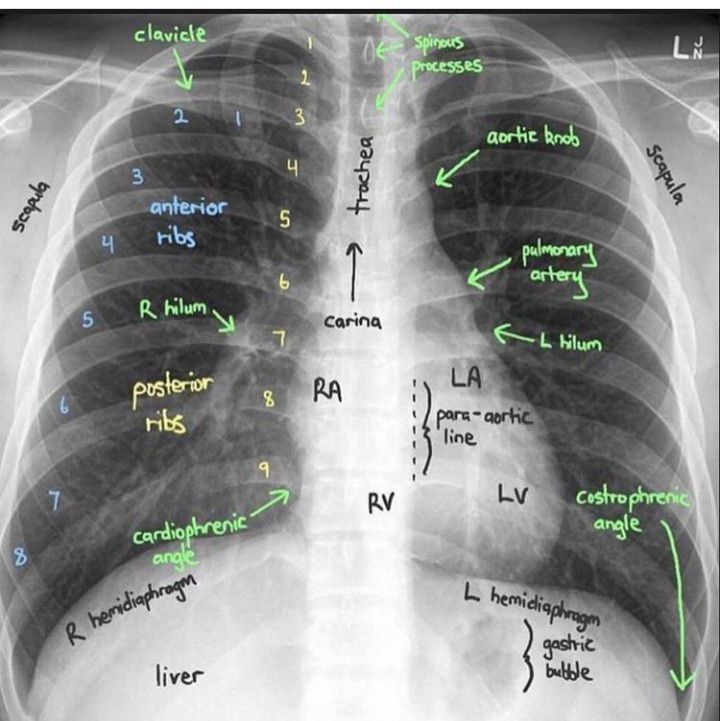

Chest X-ray Interpretation

This is the easiest explanation of chest X-ray.